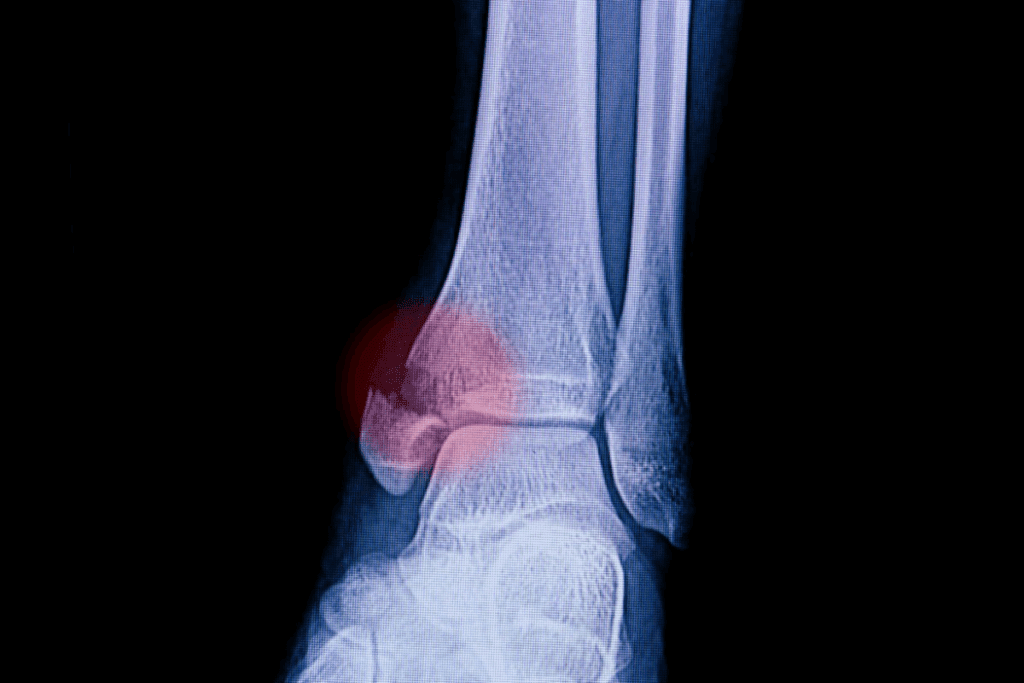

Understanding Fractures and Their Severity

It’s important to know about fractures and how serious they are. Fractures, or broken bones, can be different in how complex they are and how they affect a person.

Types of Fractures and Their Characteristics

Fractures are divided based on their severity and what they look like. The main types are:

• Simple (Closed) Fracture: The bone is broken, but the skin stays whole.

• Compound (Open) Fracture: The bone goes through the skin, making infection more likely.

• Comminuted Fracture: The bone breaks into many pieces.

• Displaced Fracture: The bone breaks, and the pieces don’t line up right.

• Non-Displaced Fracture: The bone cracks, but the pieces stay together.

Each fracture type has its own challenges and needs for treatment.

Signs and Symptoms of a Possible Fracture

It’s key to know the signs of a fracture to give the right care. Common signs include:

• Pain or tenderness in the affected area

• Swelling or bruising

• Deformity or abnormal mobility

• Difficulty moving the affected limb or area

Don’t ignore swelling or other signs that might mean a fracture. If you think someone has a fracture, don’t try to move or fix the bone.

1. Accurate diagnosis through X-rays and other imaging techniques